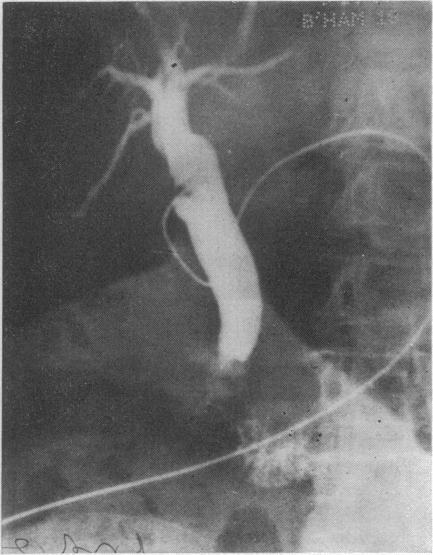

急性胆囊疾病

Acute gallbladder disease.

The pathology, clinical features, diagnosis, and management of acute cholecystitis are outlined with reference to 311 cases out of a total of 631 patients treated for gallstones over a 15-year period. Operative procedures and the choice of antibiotics are discussed.

摘要